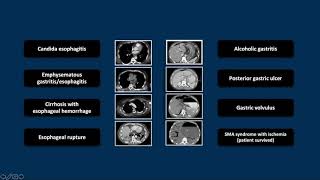

Proximal Gastrointestinal Emergencies | Interesting Radiology Cases video

Proximal Gastrointestinal Emergencies | Interesting Radiology Cases

Proximal Gastrointestinal Emergencies | Interesting Radiology Cases CT of Upper Gastrointestinal Emergencies | Free Radiology CME